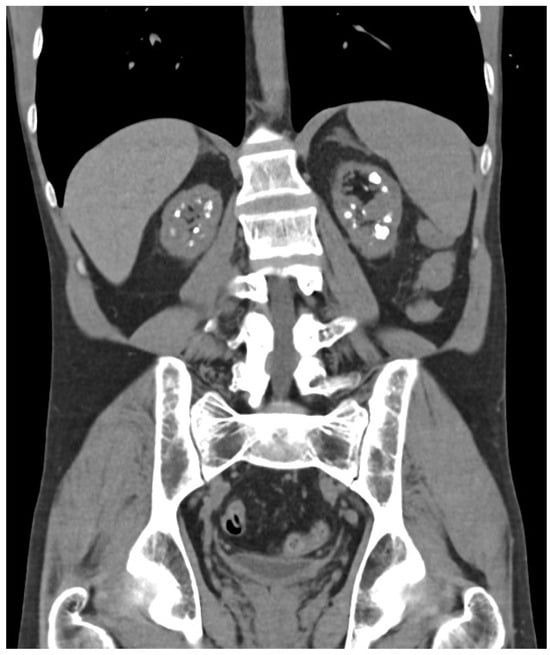

| Last imaging test | CT scan: bilateral lithiasis and microlithiasis, with nephrocalcinosis | US: bilateral microlithiasis | CT scan: atrophic kidneys with a pattern of medullary nephrocalcinosis | CT scan: microlithiasis | US: no lithiasis | CT scan: microlithiasis |